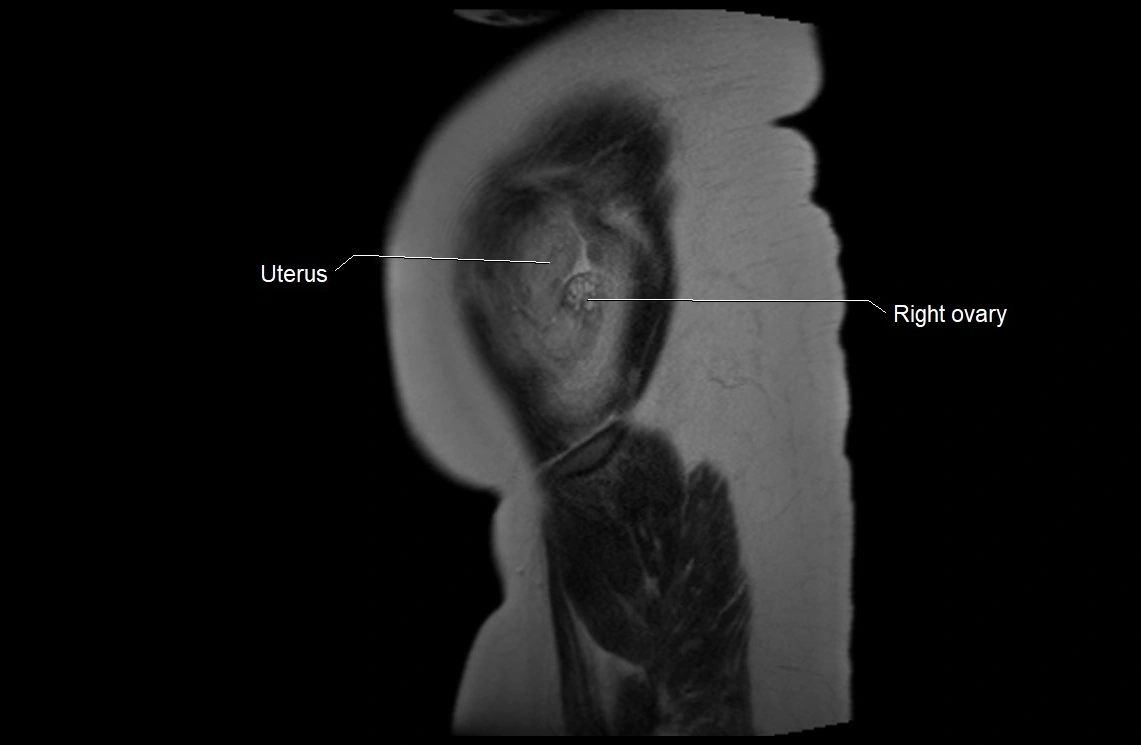

MRI Appearance

T2 HASTE (T2 GRE):

• Amniotic fluid shows very bright hyperintense signal

• Provides natural contrast against fetus and placenta

• Small particles (vernix) may appear as scattered hypointense foci within bright fluid